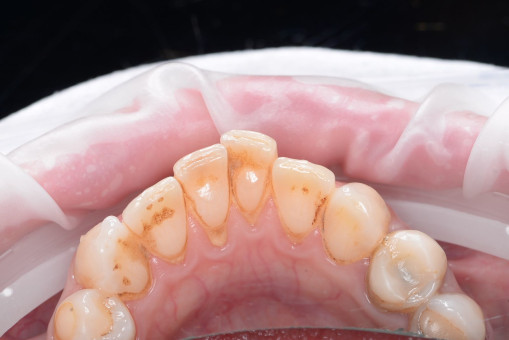

А прежде, чем вы посмотрите фотографии «до» и «после» лечения слизистой оболочки полости рта, проведенных в нашей клинике, хочу поблагодарить большое количество наших пациентов, которые поверили, прониклись нашей концепцией, и мы вместе, именно вместе победили болезни десны, гингивит и пародонтит!

До/после лечения